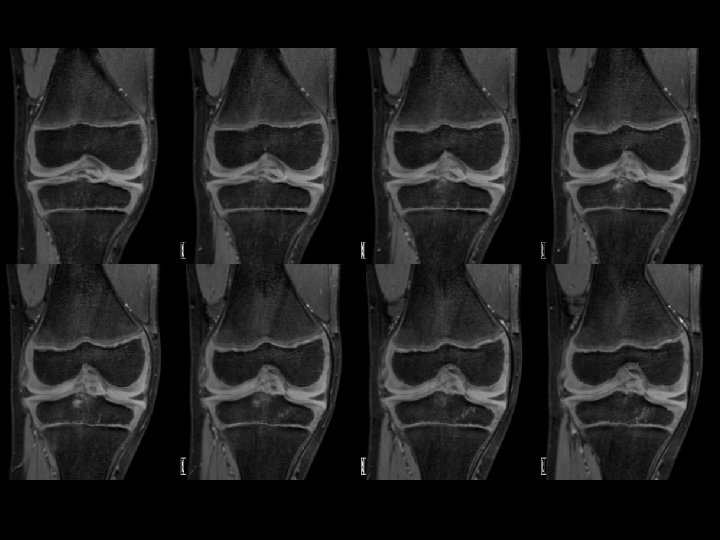

IMAGERIE • IRM : examen de choix +++ ( sédation) • Séquences : T 1, T 2 Rho Fat sat. • Connaître les particularités de l’os en croissance : Cartilage et Moëlle osseuse T Laor, D Jaramillo : MR imaging Insigths into skeletal maturation : what is normal? Radiology 2009

IRM � • Apprécier la stabilité du fragment • Cartilage articulaire • Intérêt des séquences « cartilage »

Critères pronostiques à l’IRM • Taille de la lésion +++++ • Liseré hyper intense ? ? ? • Kystes périlésionnels ?

Ménisques • Attention au signal méniscal : plus élevé que chez l’adulte, ressemble à des ménisques dégénératifs d’adultes ! • Avant 12 ans, une image linéaire centrale horizontale est un vaisseau nourricier.